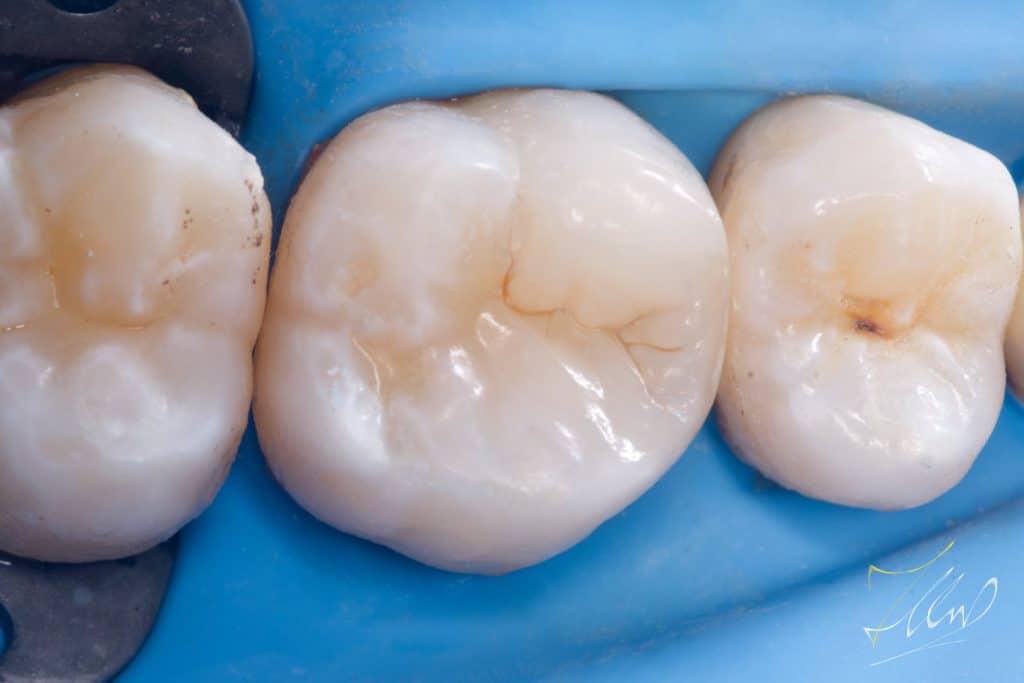

Final situation (pre polishing).

Final gloss for long lasting stain free restoration.

Buccal view shows the final contour and shape of buccal cusp.

The final palatal view demonstrates precise and secure contact placement, ensuring minimal stagnation and facilitating easy cleaning